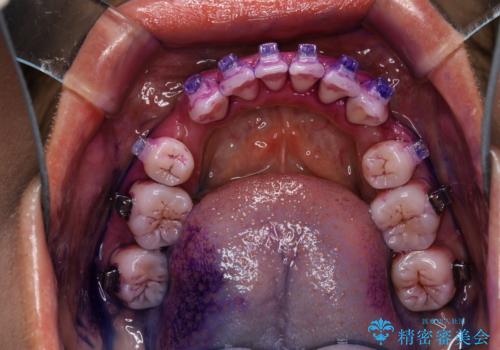

染め出しとは

口腔内にはたくさんの細菌がいるため、ヌルヌルとしたプラーク(歯垢)が自然に歯の表面に付きます。

このプラーク(歯垢)にはたくさんの細菌が潜んでおり、虫歯や歯周病・口臭などの最大の原因です。そのため、毎日の歯磨きでプラーク(歯垢)をキレイに取り除くことが、健康な歯を保つためには欠かせません。

しかし、プラークは歯の色と似ているため、見ただけでは付着しているかどうかがハッキリとは分かりません。

染め出し液を使ってプラークを染め出すことにより、普段の歯みがきで磨き残している場所を目で確かめることができます。

日々の歯磨きを上達するには、まずどこが磨けていないか認識することが大切です。